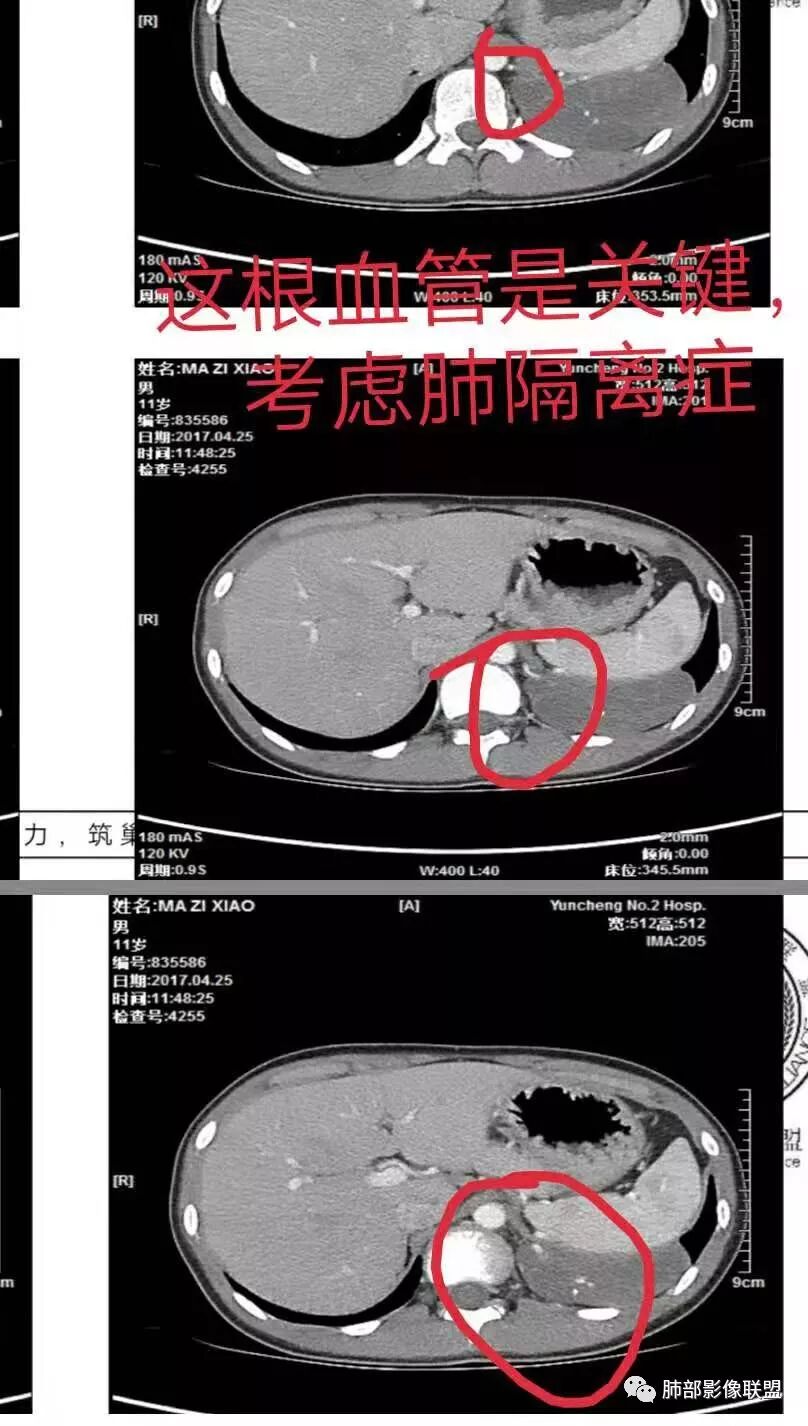

男性,11岁,为什么大家一致考虑主动脉供血来源?

1.明显主动脉供血???未见到直接征像,至少不直接了当。

2.周边血管推移的多,分隔供血需要仔细端详。有肺血管、腹部体动脉分支供血,血管较粗大,供血较丰富,肺动脉引流?肺动脉血流方向,不太符合,看看是肺动脉还是肺静脉?

左肺下叶占位,内部多发分割,内部可见供血血管(似来自腹主动脉分支),考虑:隔离症可能

左肺下叶囊性变,可见多发分隔,增强后分隔及边缘可见强化,并可见降主动脉分支进入,考虑叶外型肺隔离症

电话随访,患者在西安某医院手术,为肺隔离症,供血两支动脉,均来自腹主动脉,引流入肺静脉。

一、隔离症的血管

1.有体循环供血动脉

2.并无伴行静脉,回流到纵隔的血管不容易见到

3.相应流量的静脉,在隔离症周围通常仅有肺静脉

4.供血动脉形态有改变,常有扩张及退变